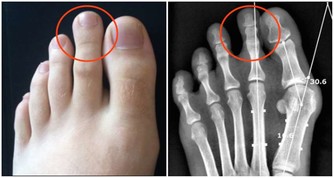

例如,如果體重指數(BMI,由體重公斤數除以身高米數的平方得出)在12到12.5之間,

問題會非常嚴重並且很快危及生命。

因為你能撐下去的時長,取決於脂肪儲備、體內的維生素和礦物質含量,以及斷食前的一般健康狀況。